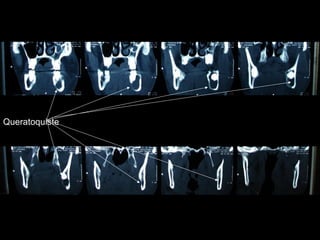

Queratoquiste odontogénico

Queratoquiste